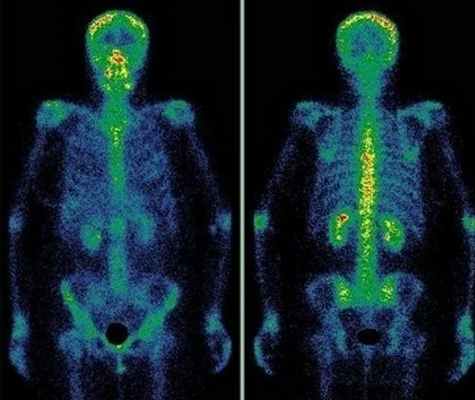

Сцинтиграфия костей скелета (остеосцинтиграфия) – исследование метаболизма (обмена веществ) костной ткани с помощью радиофармацевтических препаратов (РФП), которые накапливаются в костях скелета. Радиофармпрепарат вводится внутривенно и затем излучение от накопившегося препарата улавливается детекторами регистрирующего прибора (гамма-камеры).

Что и как показывает сцинтиграфия костей скелета

С помощью сцинтиграфического обследования врачи выявляют различные патологии, недоступные другим диагностическим методам:

Диагностику заболеваний костей скелета проводят с меченными фосфатными комплексами, которые прочно связываются с кристаллами гидроксиапатита и незрелым коллагеном. В качестве метки используется 99мТс, который имеет короткий период полураспада – всего 6 ч. Гамма-кванты покидают организм и регистрируются детекторами прибора, в результате после компьютерной обработки получается изображение.

Метастазы различных опухолей в кости

Многие опухоли метастазируют в кости. В первую очередь подозрение на метастатическое поражение скелета возникает при раке молочной и предстательной желез, раке легкого и почек. Особую настороженность следует проявлять при увеличении уровня онкомаркеров ПСА (простатспецифический антиген), СА 15-3 и некоторых других. После консервативного лечения или хирургического удаления опухоли рекомендуется динамическое наблюдение за состоянием костной ткани. Сцинтиграфию следует проводить первые 2 раза с промежутком 6-8 месяцев, затем, при нормальном результате исследования - через 1–2 года.

4. Радионуклидные исследования:

• Остеосцинтиграфия:

о «Холодный» очаг в кости на ранней стадии

о По мере излечения, захват неоднородно повышается